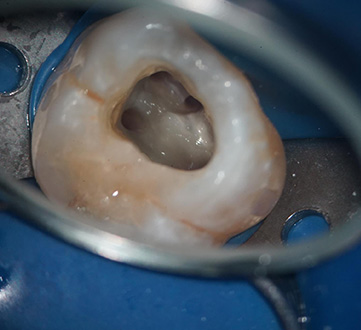

※マイクロスコープ治療時写真

根管は非常に細く複雑な構造をしているため、肉眼ではすべてを確認するのが困難です。しかし、マイクロスコープを使用することで、感染部分を的確に除去し、再発リスクを大幅に低減できます。従来の治療に比べ、より精度の高い根管治療が可能になり、「抜歯しかない」と診断された歯でも残せる可能性が高まります。

特に根管治療(歯の神経治療)においては、マイクロスコープの使用が大きな利点となります。根管の内部は非常に細く複雑な構造をしているため、従来の肉眼やルーペでは完全な処置が難しい場合があります。しかし、マイクロスコープを用いることで、感染部分を確実に除去し、再発リスクを大幅に低減できます。